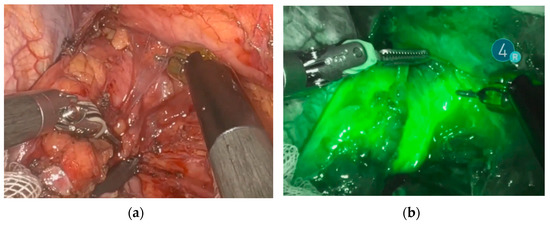

2.5. ESOMAP Protocol